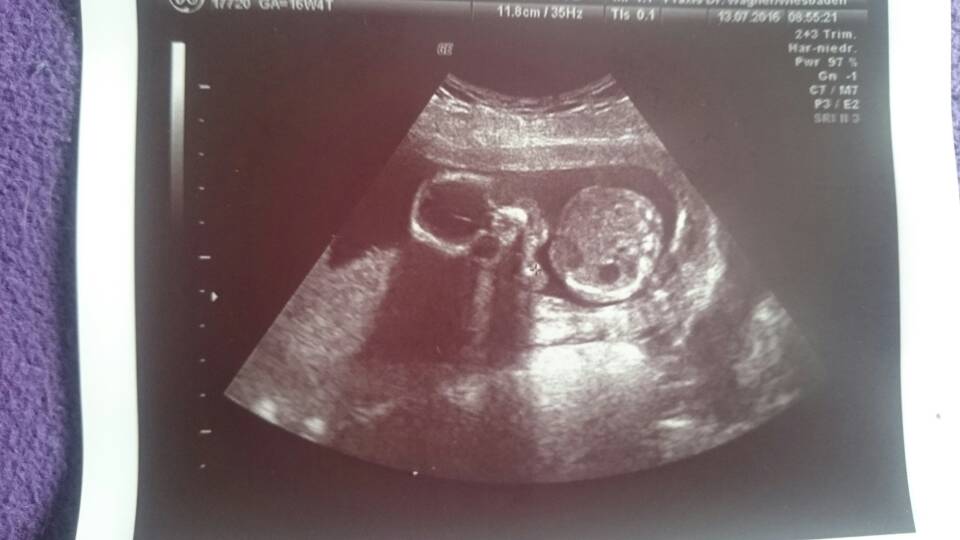

Tak więc dzidziuś ma się bardzo dobrze, ma piękne bijące serduszko, waży 150g, ma silne rączki i nóżki które odpychaly się od głowicy usg.przez co nie za bardzo dał się podglądać. Lekarz usilnie próbował zobaczyć czy Fabian został Fabianem, no ale było tak ułożone poprzecznie że ani dopochwowo ani przez brzuch nie pokazało się nam w pełnej okazałości. Lekarz mówił że z tym synem to mógłby sie trochę poklocic, bo to co dziś udało mu sie podglądać wcale aż takie chłopięce nie było. I szansę na Lene wzrosły. Cierpliwie tłumaczył, ze za 4 tyg będę miała usg polowkowe i takie badanie bedzie trwało ok 30-40 minut więc mamy szansę żeby dzidziuś pobracal sie trochę co da nam więcej możliwości zagladnac między nogi.

To co dziś zobaczył to nie było aż tak bardzo chłopięce, i bardziej przypominało mu spuchniete wargi. Ale ze dojście miał ciulowe do krocza mojego dziecka to nie chciał określać płci dziś.

Szyjka bardzo długa, łożysko wysoko zdala od ujścia szyjki. Plamienia mogą się jeszcze pojawiać do 20 tyg i mam być spokojna, bo o ile nie ma krwi to jest bardzo dobrze.